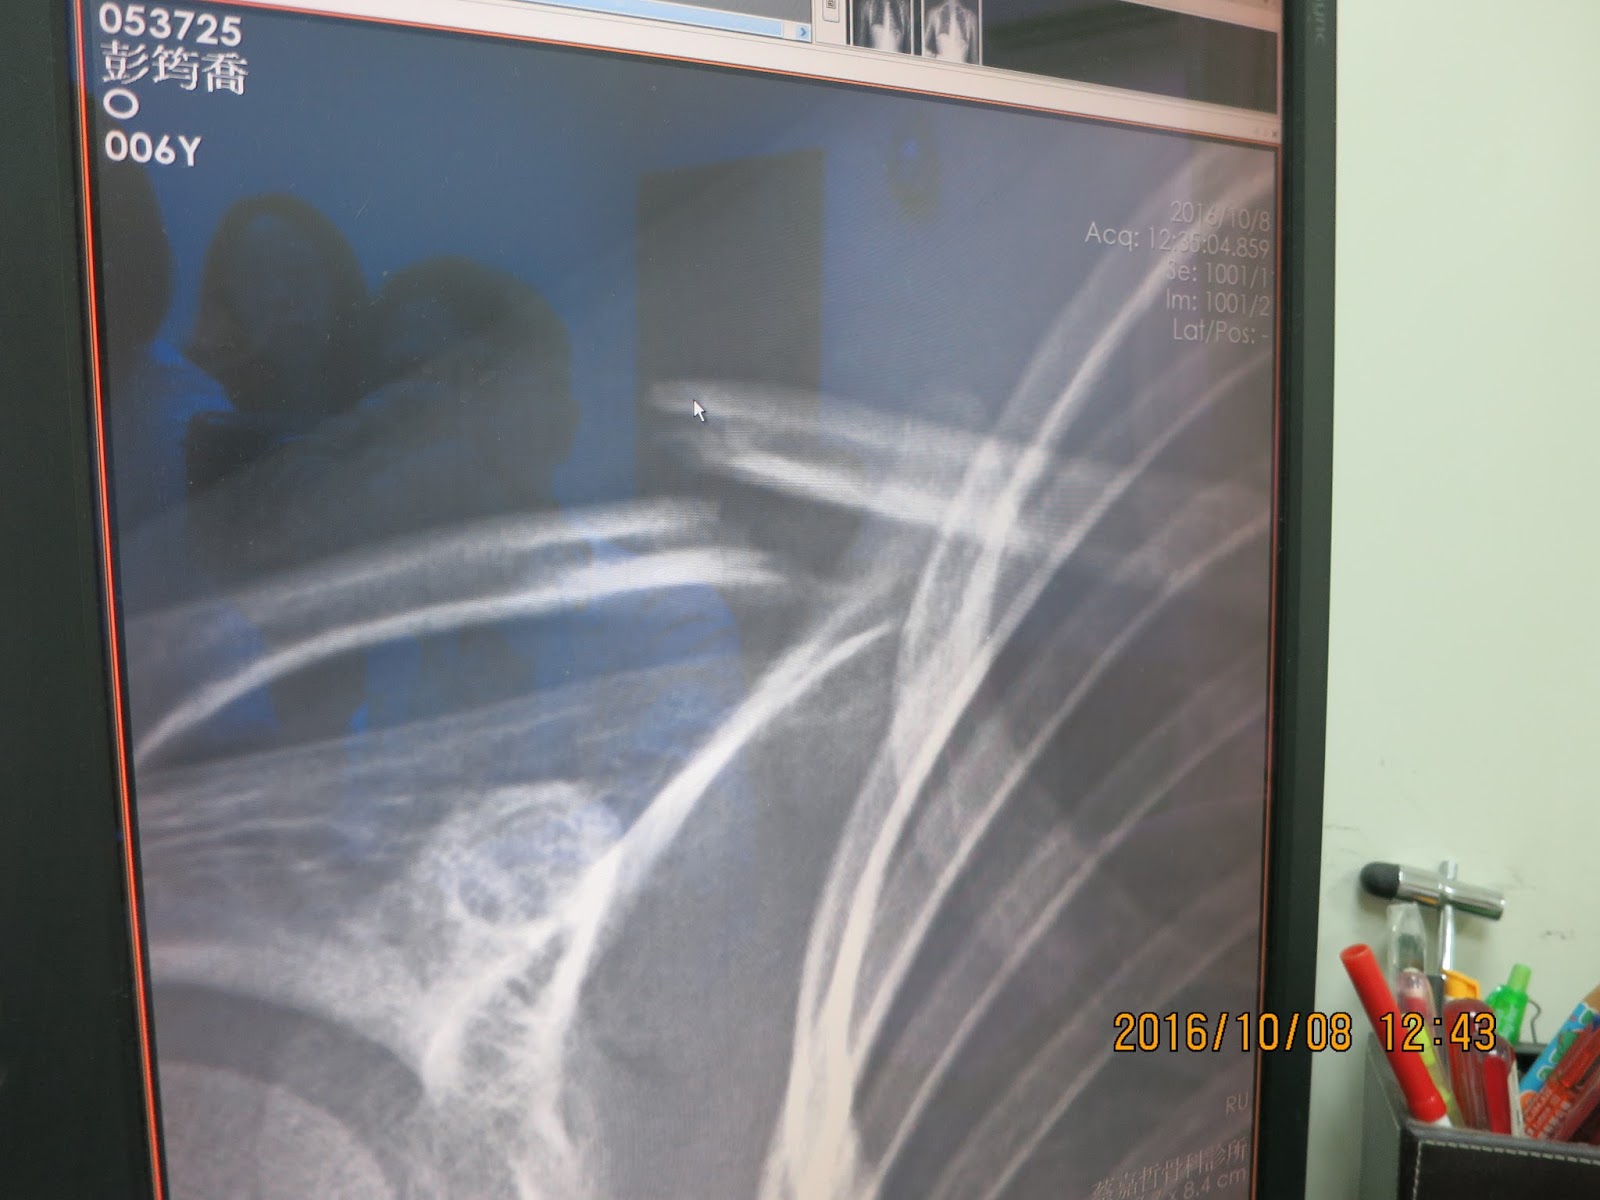

這X光片真的嚇到我了,鎖骨斷裂,難怪小牛妹妹這麼痛

要上固定帶